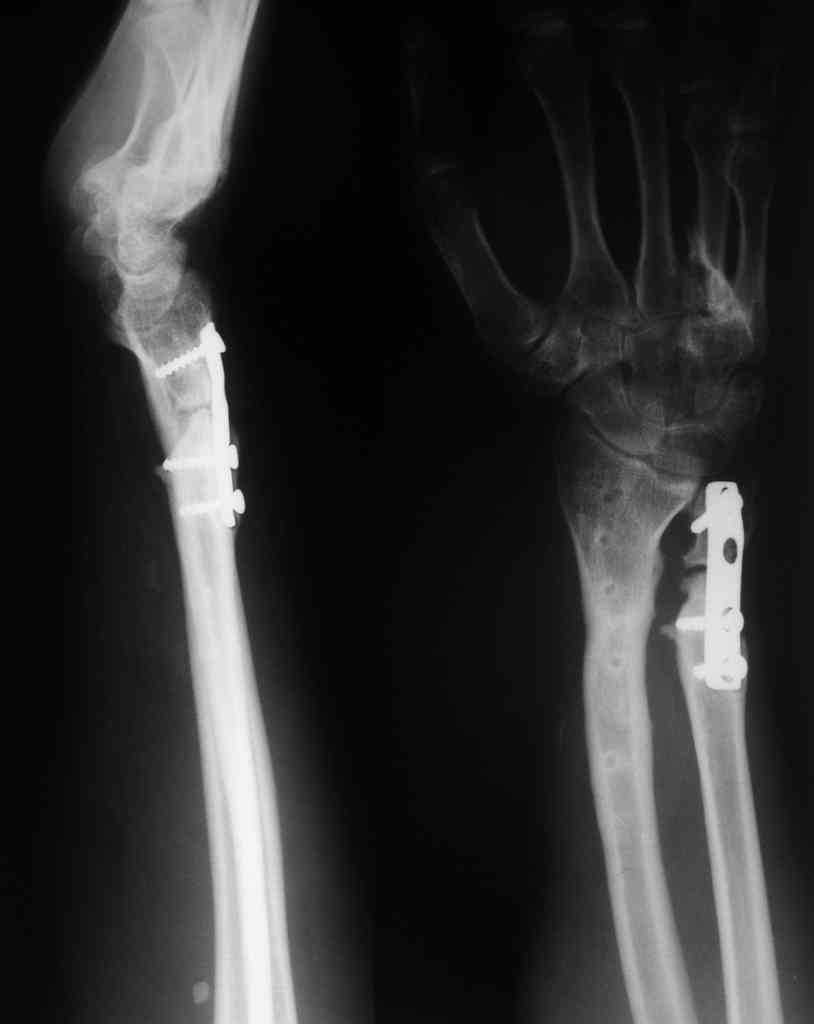

Обратился пациент 22 лет. Открытый перелом 5 лет назад в Венгрии,

там сделали остеоинтез пластинами, кожные пластики. В прошлом году

убрали пластинку с лучевой стороны. Из локеовй не стали убирать из-за

несращения (см. снимок). У боьного также контрактура лучезапястного

сустава (сгибание 60/0/10 разгибание)и ротационная (пронация

70/0/0супинация). Пацинт хочет улучшить движения, ну и добиться

сращения локтевой. Воникают мысли о костной пластике локтевой,

"разгибательной" остеотомии  лучевой. Как полагаете, чем тут лучше

помочь?